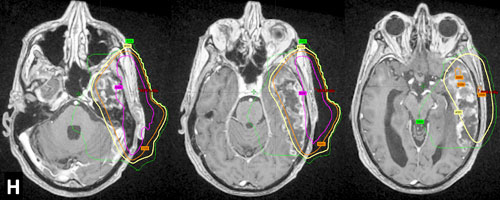

The study was performed on 22 people who were undergoing radiation treatments for a family of brain tumors known as gliomas. 14 participants were being treated for glioblastoma, three for grade 3 gliomas, and five for low-grade gliomas. The researchers conducted a dose-volume histogram analysis in order to estimate how much radiation each patient received to several different regions of the head, including the thalamus, temporal lobes, nasopharynx, olfactory groove, frontal pole and periventricular stem cell niche. Participants were asked to complete a questionnaire assessing any smell or taste disturbances at the beginning of the study (prior to radiation), as well as at three and six weeks after the beginning of radiation treatment.

The researchers found that an increased radiation dose to the nasopharynx was associated with a significantly increased risk of taste disturbances. Although not technically part of the brain, the pharynx is an organ inside the head that plays important roles in both digestion and respiration. The nasopharynx is the topmost part of this organ and sits just behind the nose.

The researchers further found that, when patients with tumors of the temporal lobes did experience taste disturbances, these disturbances were much more severe than those experienced by other patients. These more severe taste disturbances might have been caused by the tumor itself, or as a side effect of having radiation applied directly to the temporal lobe.